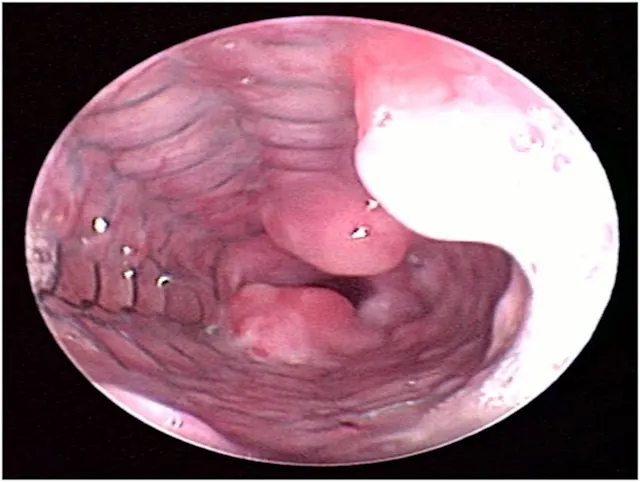

Tracheoscopy, the gold standard for diagnosing tracheal collapse, enables direct viewing of the trachea and mainstem bronchi, quantification of severity and extent of collapse, identification of concurrent inflammation, and collection of tracheal or bronchial samples for culture and cytology. With tracheoscopy, tracheal collapse can be categorized based on the Tangner and Hobson grading system with grades I, II, III, and IV characterized by 25%, 50%, 75%, and 100% collapse, respectively16 (Figure 2). Disadvantages include limited availability, cost, and need for general anesthesia. Because veterinary patients may be small, tracheoscopy is often performed under injectable anesthesia and without intubation; as such, ventilation cannot be assisted during the procedure, and oxygen must be supplemented through the endoscope or with an intratracheal catheter. Some dogs with severe tracheal collapse develop dyspnea and cyanosis during anesthetic recovery.

Endoscopic view of tracheal collapse: Grades I–IV (A-D) of tracheal collapse, respectively. Used with permission.23